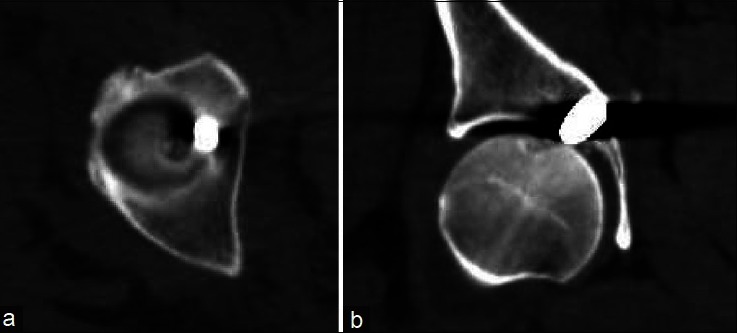

与标准的开放式关节切开术相比,髋关节镜已被证明能以微创方式进入髋关节。关节镜在诊断和治疗髋关节疾病方面的应用在不断发展。本研究描述了一个在关节镜下取出低速枪伤子弹的病例。患者的枪伤进入腹部,穿过小肠和乙状结肠,然后穿透膀胱,最后进入髋臼内侧壁。在对内脏进行手术修复后,使用标准关节镜门户和骨折台从髋关节中取出了子弹。决定使用关节镜的原因有很多。最重要的是需要最大限度地减少软组织剥离,这是取出子弹所必需的,同时又不影响耻骨上区域之前的伤口。在进行手术之前,还考虑了子弹碎片和移位的潜在风险,以及可能出现的腹腔隔综合征。关节镜手术可以充分检查关节表面、冲洗关节并取出异物,同时避免了侵入性关节切开术及其相关的发病率和软组织破坏。这种手术技术为这名患者带来了非常满意的结果,并为其他遇到类似损伤模式的外伤患者提供了范例。对于有髋关节镜手术经验的外科医生来说,这种手术可以安全、快速地进行,而且并发症极少。

Hip arthroscopy has been shown to offer minimally invasive access to the hip joint compared with standard open arthrotomy. The use of arthroscopy for diagnosing and treating disorders about the hip continues to evolve. This study describes a case that involves arthroscopic removal of a bullet from a low-velocity gunshot wound. The patient sustained a gunshot wound that entered the abdomen and traversed the small bowel, sigmoid colon then penetrated the urinary bladder before ending up in the medial wall of the acetabulum. After surgical repair of the viscus, the bullet was retrieved from the hip joint using standard arthroscopic portals and a fracture table. A number of issues led to the decision to use arthroscopy. Most importantly was the need to minimize soft tissue dissection, which was required to access the bullet, without interfering with previous wound at the suprapubic area. The risks of potential bullet fragmentation and migration, as well as a possible abdominal compartment syndrome were considered before proceeding. Arthroscopy allowed adequate inspection of the articular surface, irrigation of the joint, and removal of the foreign body while avoiding an invasive arthrotomy with its associated morbidity and soft tissue disruption. This surgical technique afforded a very satisfactory outcome for this patient and serves as a model for others when encountering a similar injury pattern in a trauma patient. It is a procedure that can be performed safely, quickly, and with minimal complications for surgeons with experience in arthroscopy of the hip joint.